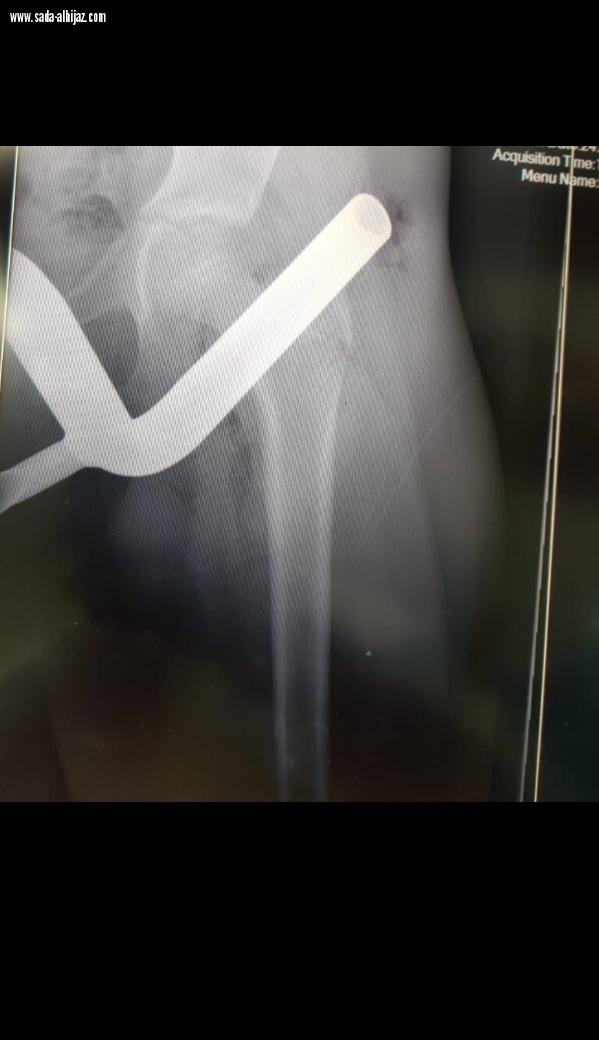

تمكن فريق طبي متخصص بجراحة العظام بمستشفى الملك فهد العام بالمدينة المنورة من إخراج قطعة معدنية تجاوز طولها 20 سم من فخذ شاب يبلغ من العمر 13 عاماً بعد ان خرجت من دراجته الهوائيه .

وبين الدكتور بسام الأحمدي أستشاري جراحة العظام بالنيابه بالمستشفى حضر المصاب الى طواريء المستشفى بواسطة الإسعاف بعد إصابته بجزء معدني خرج من دراجته الهوائية التي كان يستقلها فأنغرس في فخذ الشاب وقام الدفاع المدني بفصل الدراجة عن الجزء المنغرس بالقدم ونقل المريض للمستشفى .

و واضح الدكتور بسام على الفور تدخل الفريق الطبي بالطواري لتجهيز المريض لغرفة العمليات بشكل عاجل ، وبعد أخذ الفحوصات والأشعة اللازمة للإستطلاع ما اذا كان هناك اي كسور في عظمة الفخذ او إصابة للشرايين والأوردة والأعصاب المغذية حيث ان الجسم المعدني كان قريباً منها بمسافة ٥ سم فقط ، والتي اظهرت الأشعة بلطف الله عدم تعرضها لأي أذاء

وأكد الأحمدي أُدخل المصاب الى غرفة العمليات وتم تخديره بشكل كامل وإخراج القطعه المعدنية من فخذه في وقت وجيز لم يتجاوز 10 دقائق ، وتم نقل المريض بعد الإفاقة الى قسم التنويم ومتابعة الحالة قبل أن يغادر المستشفى بصحة جيده بعد 72 ساعة من العملية .